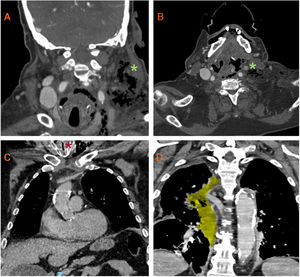

We report the case of a 68-year-old male with chronic obstructive pulmonary disease (COPD) admitted for progressive dyspnea and left cervical swelling. During hospitalization, his respiratory status worsened, with increased oxygen requirements. Cervicothoracic computed tomography (CT) scan (video) revealed subcutaneous emphysema with air bubbles in the left laterocervical soft tissues (Fig. 1A), a left cervical abscess, extensive thrombosis of the left internal jugular vein and ipsilateral dural venous sinuses (Fig. 1B), and contralateral tracheal deviation narrowing the glottic lumen to 5mm (Fig. 1C). The abscess extended into the mediastinum, causing acute right mediastinitis and severe airway compromise (Fig. 1D). An emergency surgical tracheotomy was performed, followed by cervical drainage and intravenous antibiotics (amoxicillin/clavulanic acid and clindamycin). Cultures were negative. Despite treatment, the patient's condition progressively deteriorated and he died. Descending mediastinitis secondary to cervical abscess is almost always linked to prior oral manipulation or infection [1,2]. Only one similar idiopathic case without oral intervention has been reported [1]. This case emphasizes the severity of descending mediastinitis and the need for prompt diagnosis and treatment, even in the absence of typical risk factors.

Cervicothoracic CT scan demonstrating: (A) subcutaneous emphysema with air bubbles in the left laterocervical region (green asterisk); (B) cervical abscess accompanied by extensive thrombosis of the left internal jugular vein and ipsilateral dural venous sinuses (green asterisk); (C) severe airway deviation with a minimum glottic lumen diameter of 5mm (red asterisk); and (D) cervical collection with mediastinal extension (highlighted in yellow), responsible for right-sided mediastinitis and significant airway compromise.